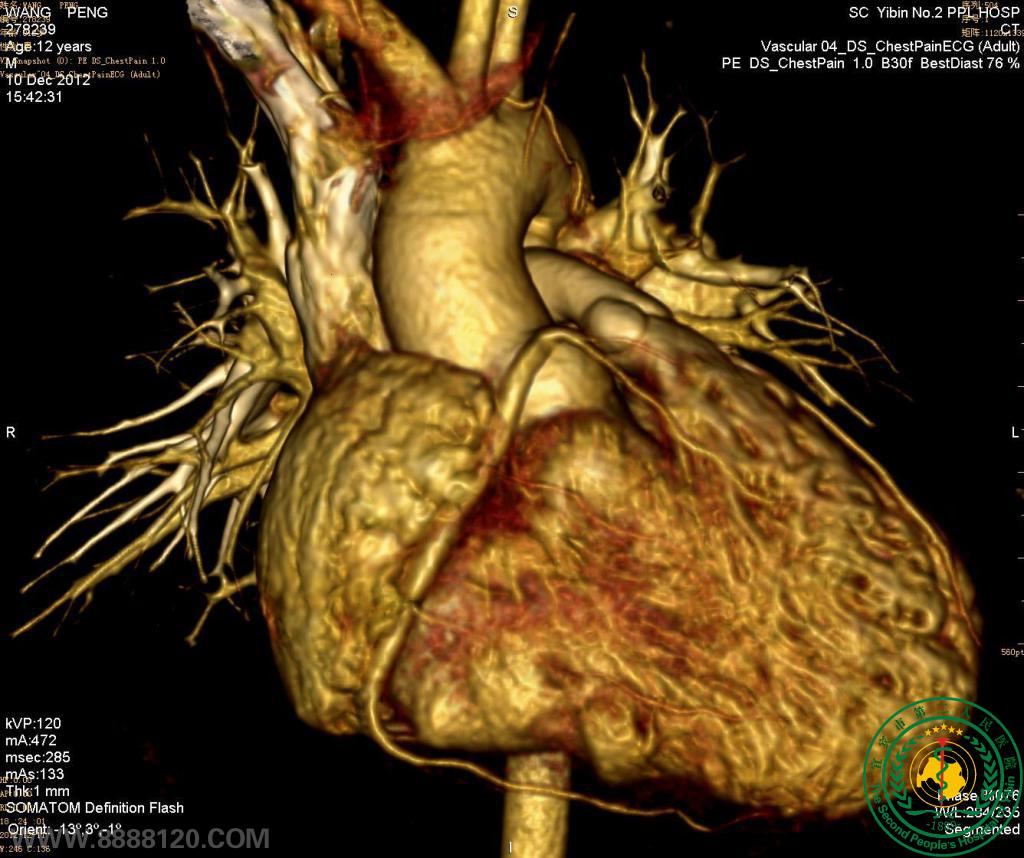

我院炫速双源CT正式投入使用第二周,今天即对1例高心率(114次/分钟)法洛氏五联症合并动脉导管未闭患者作了心脏、冠状动脉、主动脉和肺动脉检查,一次扫描,快速、准确诊断。

1.右心室增大,室间隔干下部缺损,房间隔卵圆孔缺损,主动脉骑跨室间隔,肺动脉主干和右室流出道狭窄,诊断为法洛氏五联症,双侧下肺动脉明显加宽。

2.主动脉弓和肺动脉主干间见通道,诊断为动脉导管未闭。

3.左、右冠状动脉未见异常。

炫速双源CT(又称第二代双源CT或新双源CT)与128排、320排CT比较,其时间分辨率最高,达75ms,在显示心腔外解剖结构,如肺动脉、肺静脉、冠状动脉、主动脉弓降部和降主动脉有体肺侧支的发育及畸形时具优势。临床应用经验证明,DSCT能准确显示婴幼儿的心血管解剖,特别有利于复杂型先天性心脏病的节段分析,以提供诊断和手术依据,在心脏与内脏关系、房室连接关系、大血管起止排列关系、肺动脉发育状况、冠状动脉发育状况、主动脉弓发育状况及肺静脉畸形引流诊断方面具有优势。婴幼儿进行心导管检查受限,但行CT检查也要考虑其辐射剂量问题。对于婴幼儿我们采用大螺距前瞻性心电门控技术(即新双源CT特有的炫速螺旋扫描),其可使检查有效辐射剂量由回顾性门控的平均5.0 mSv降到0.7 mSv左右,值得临床推广应用。